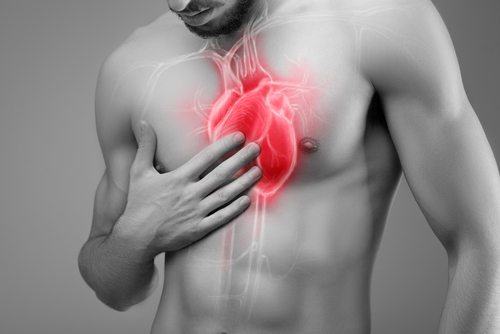

Rezultati pretrage za: angina pectoris